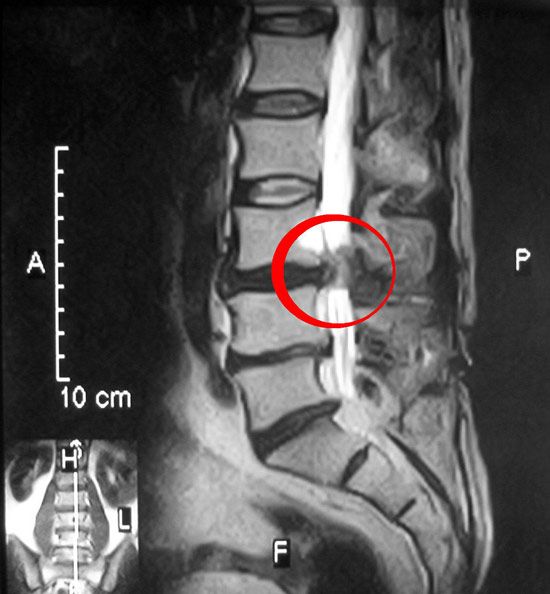

- Магнитно-резонансная томография (МРТ). Для создания изображений вашего тела используется магнитное поле. Это исследование применяется для подтверждения локализации грыжи межпозвоночного диска и определения пораженных нервов. МРТ является золотым стандартом диагностики грыж межпозвонковых дисков.

Часто грыжа межпозвоночного диска может существовать безсимптомно, не проявляя себя. Доказательством этого являются частые случаи выявления грыжи на магнитно-резонансных томограммах (МРТ) у пациентов, не имеющих никаких жалоб.